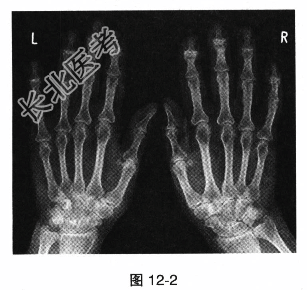

- [材料题] 患者女,62岁。右手第一腕掌关节疼痛肿胀3个月,劳累后加重,休息后可有减轻,手部照片及X线见图12-2。

- 多项选择题1.该患者最可能的诊断是

A、类风湿关节炎

B、骨关节炎

C、痛风性关节炎

D、莱姆病

E、化脓性关节炎

F、强直性脊柱炎

- 多项选择题2.骨关节炎导致的第一腕掌关节的畸形,称为

A、赫伯登结节

B、布夏尔结节

C、方形手

D、梭样畸形

E、鹅颈样畸形

F、纽扣花样畸形